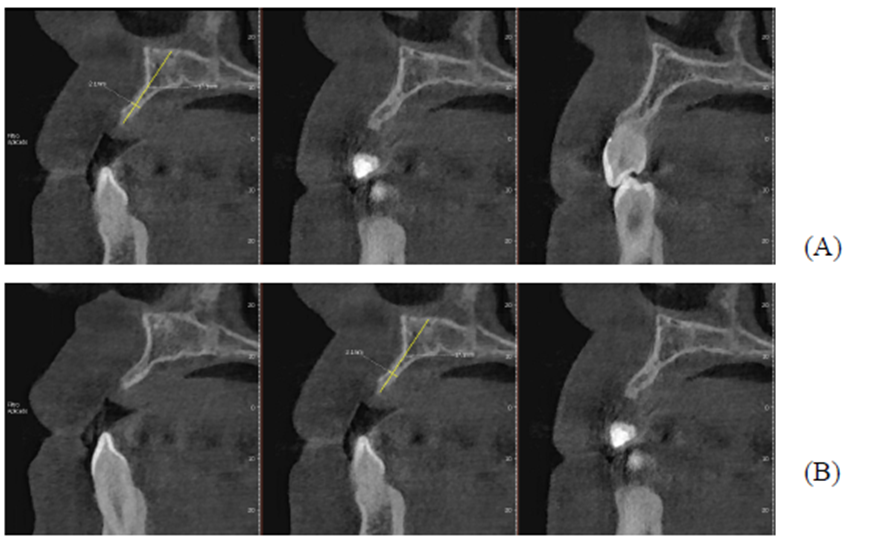

Figuras A,B,C, D e E: imagens evidenciando grande perda óssea anterior no sentido horizontal, bem como a vestibularização do rebordo anterior, o que impossibilita a instalação dos implantes em um bom posicionamento tridimensional.

Após oito meses, foi realizada outra tomografia computadorizada (TC) na própria clínica escola, onde foram realizadas medidas de altura e espessura evidenciando grande ganho ósseo horizontal. Não ocorreu quaisquer tipos de complicação no pós-operatório tardio. (Figuras 1-A, 1-B, 1-C, 1-D).